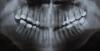

vitaly. Опубликовано 18 октября, 2011 Поделиться Опубликовано 18 октября, 2011 (изменено) Пятый зуб сверху, справа ноет при постукивании врачом..и иногда самопроизвольно поднывает. Сделала свой снимок(малюсенький, и как там вообще можно что-то увидеть) и сказала что там гранулемка, удалять мол надо! Я не хочу удалять! Можно его вылечить? И как это лучше сделать? Зуб мервый , по большей своей части состоит из пломб... Изменено 18 октября, 2011 пользователем vitaly. Ссылка на комментарий

Scrabble Опубликовано 18 октября, 2011 Поделиться Опубликовано 18 октября, 2011 Судя по этому снимку, от зуба уже мало что осталось. Можно убрать пломбу и посмотреть, возможно ли после перелечивании восстановить вкладкой и коронкой. Если нет, тогда только удалять. Ссылка на комментарий

Scrabble Опубликовано 20 октября, 2011 Поделиться Опубликовано 20 октября, 2011 (изменено) Если болит, значит, есть периапикальный процесс. Или трещина, перфорация... Изменено 20 октября, 2011 пользователем Scrabble Ссылка на комментарий